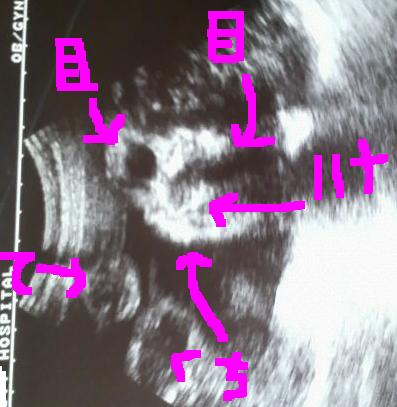

ちょうど顔がはっきり映ってる所を撮ってくれたんだよ~

コレダ!!

ジローのお顔♪  お顔解説w

どう?(*´∀`)

鼻がねぇ~アオサンそっくりなの!!